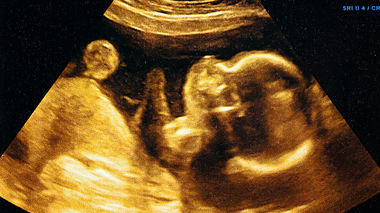

3. Can sonography scans show eyebrows and eyelashes?

In most routine scans, these fine details aren't clearly visible. Their development is usually confirmed after birth.